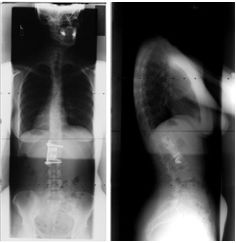

The day after her accident, Teresa had an L1 corpectomy, a surgical procedure that involves the removal of all or part of the intervertebral disc, combined with placement of a titanium cylindrical cage, an interbody fusion device, and a z-rod from the T12 to L2 vertebrae. At the time of her surgery, the use of the titanium prosthesis was a relatively new procedure.

These x-rays taken from the front (left) and side (right) show the titanium prosthesis that replaced vertebrae in Teresa's spine.